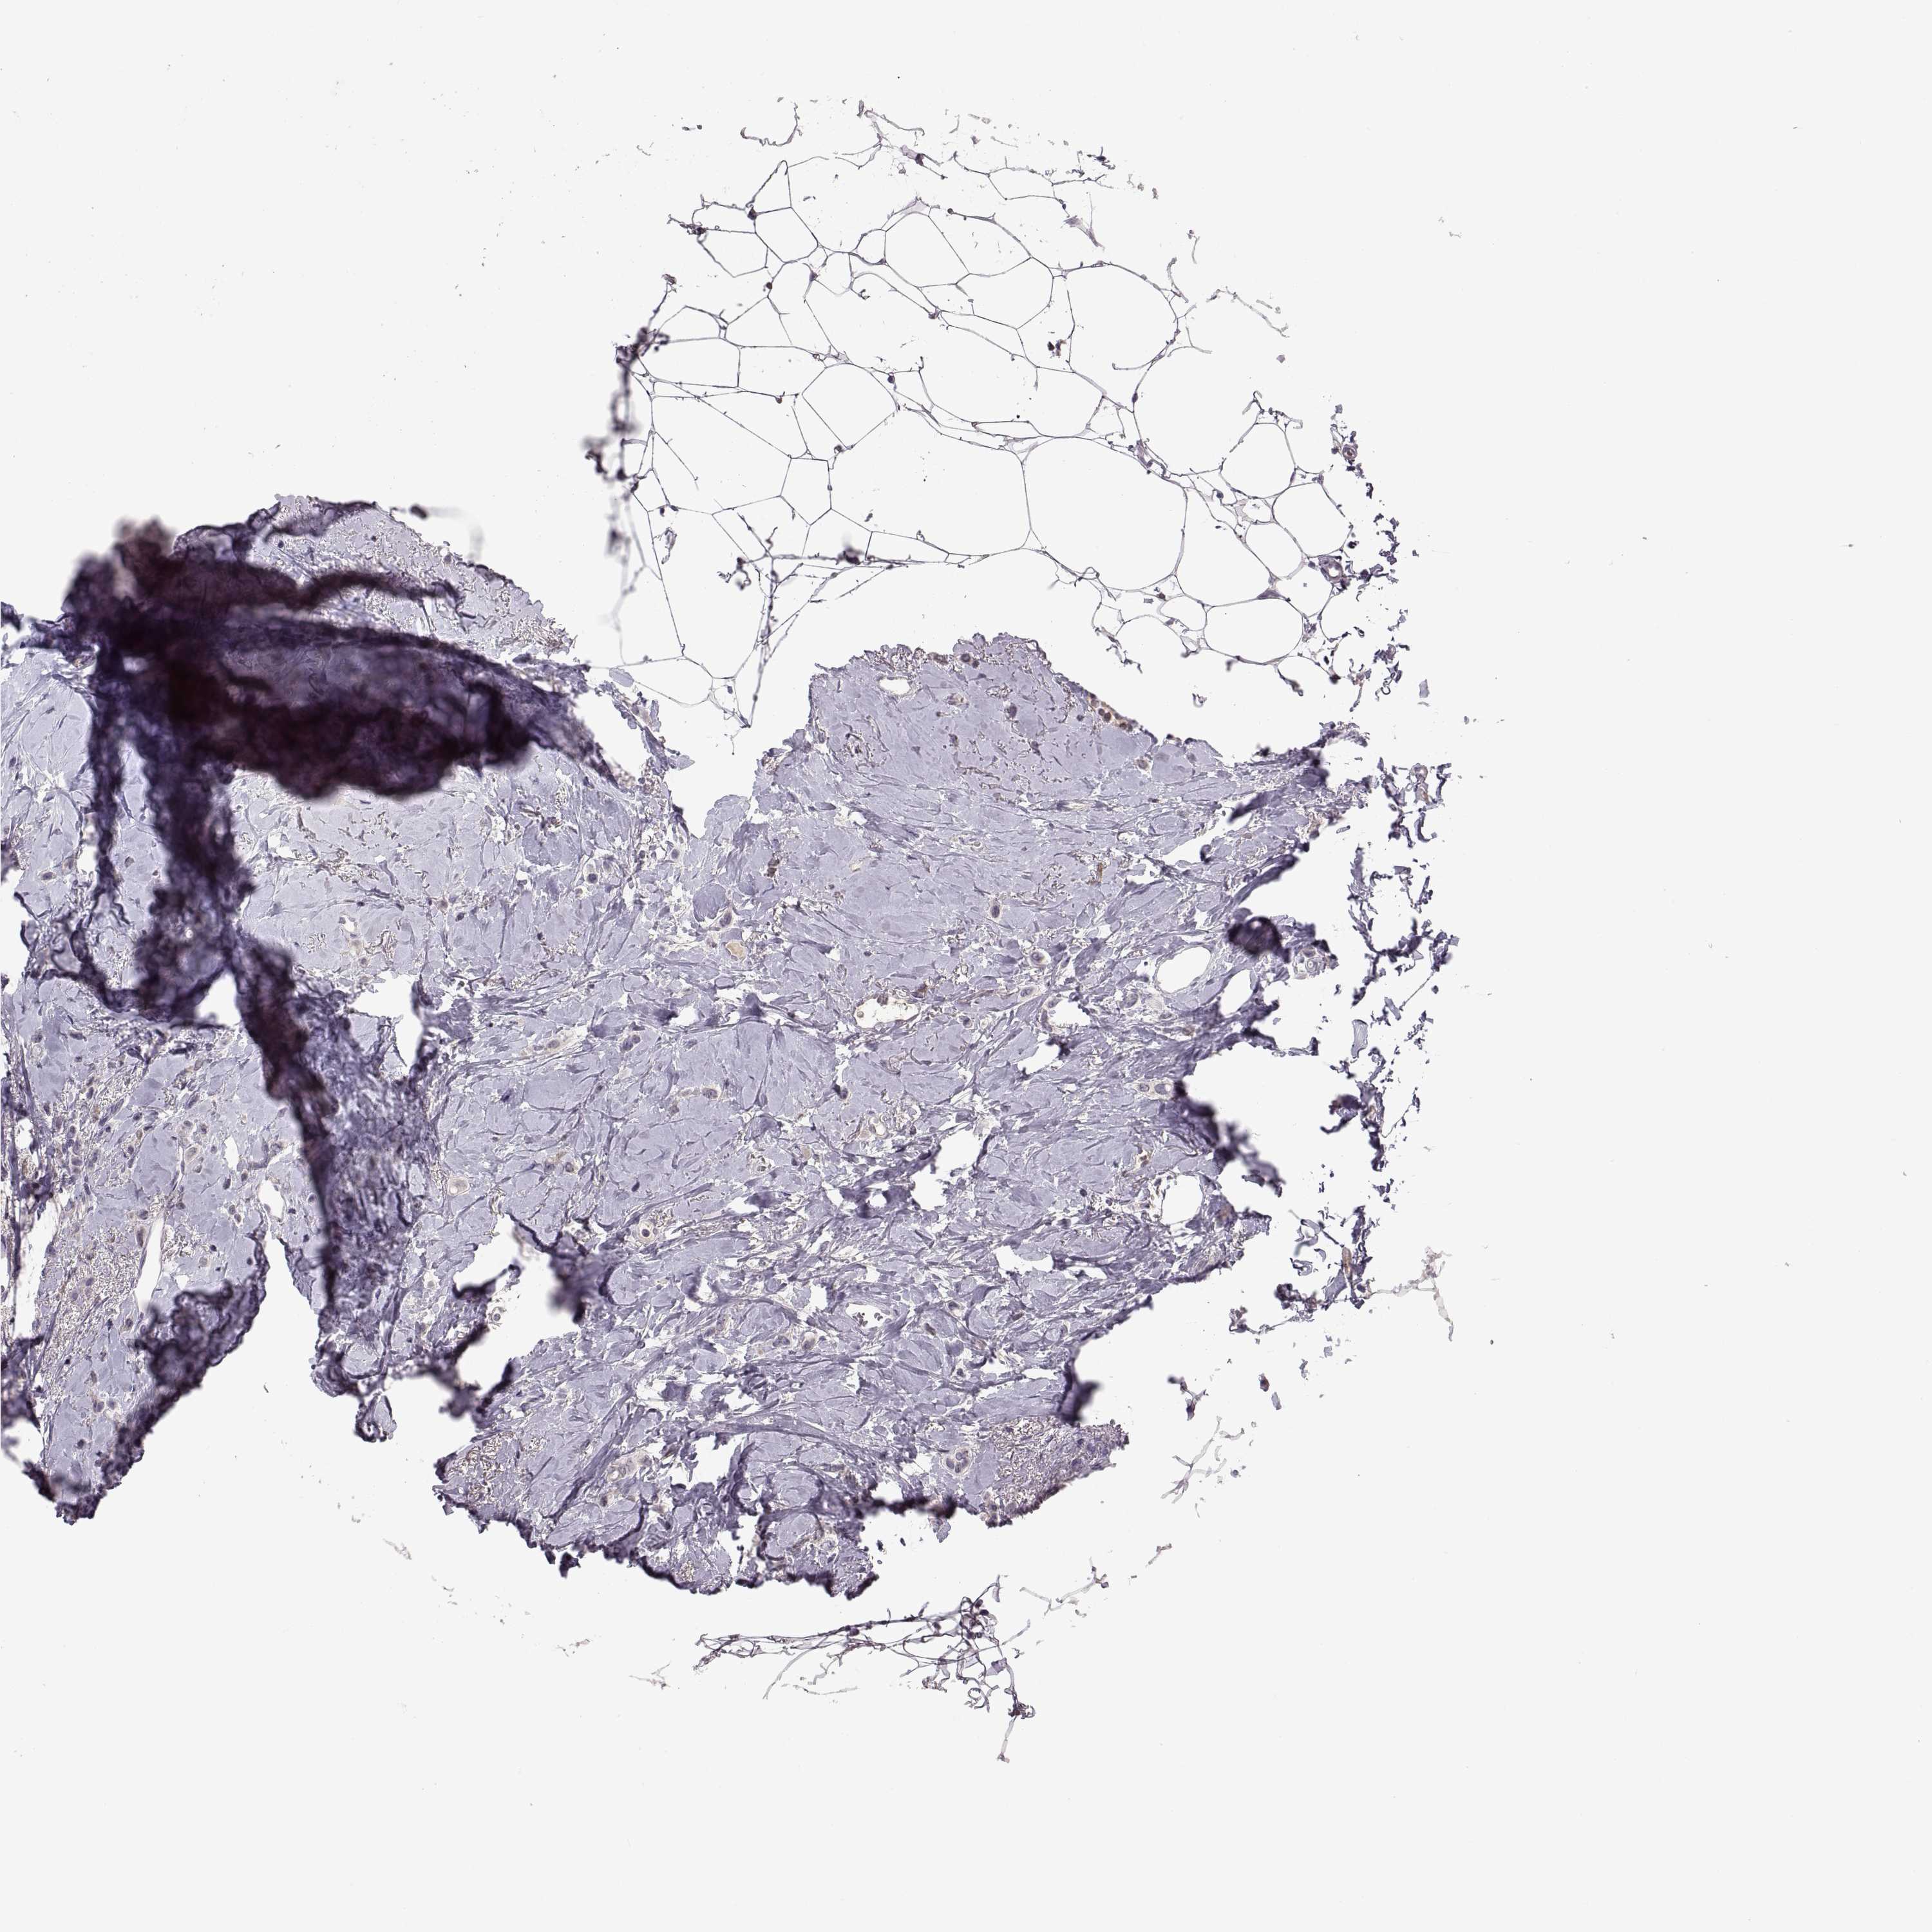

BRCA TCGA BRCA VALIDATION PROTEIN EXPRESSION